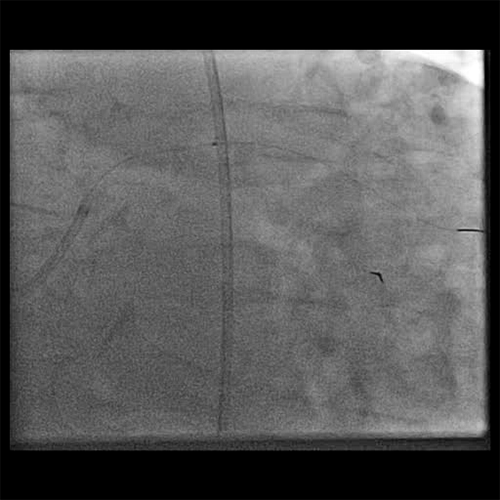

• Angiographic improvement was observed post thrombectomy (Cine 4: Post FETCH2)